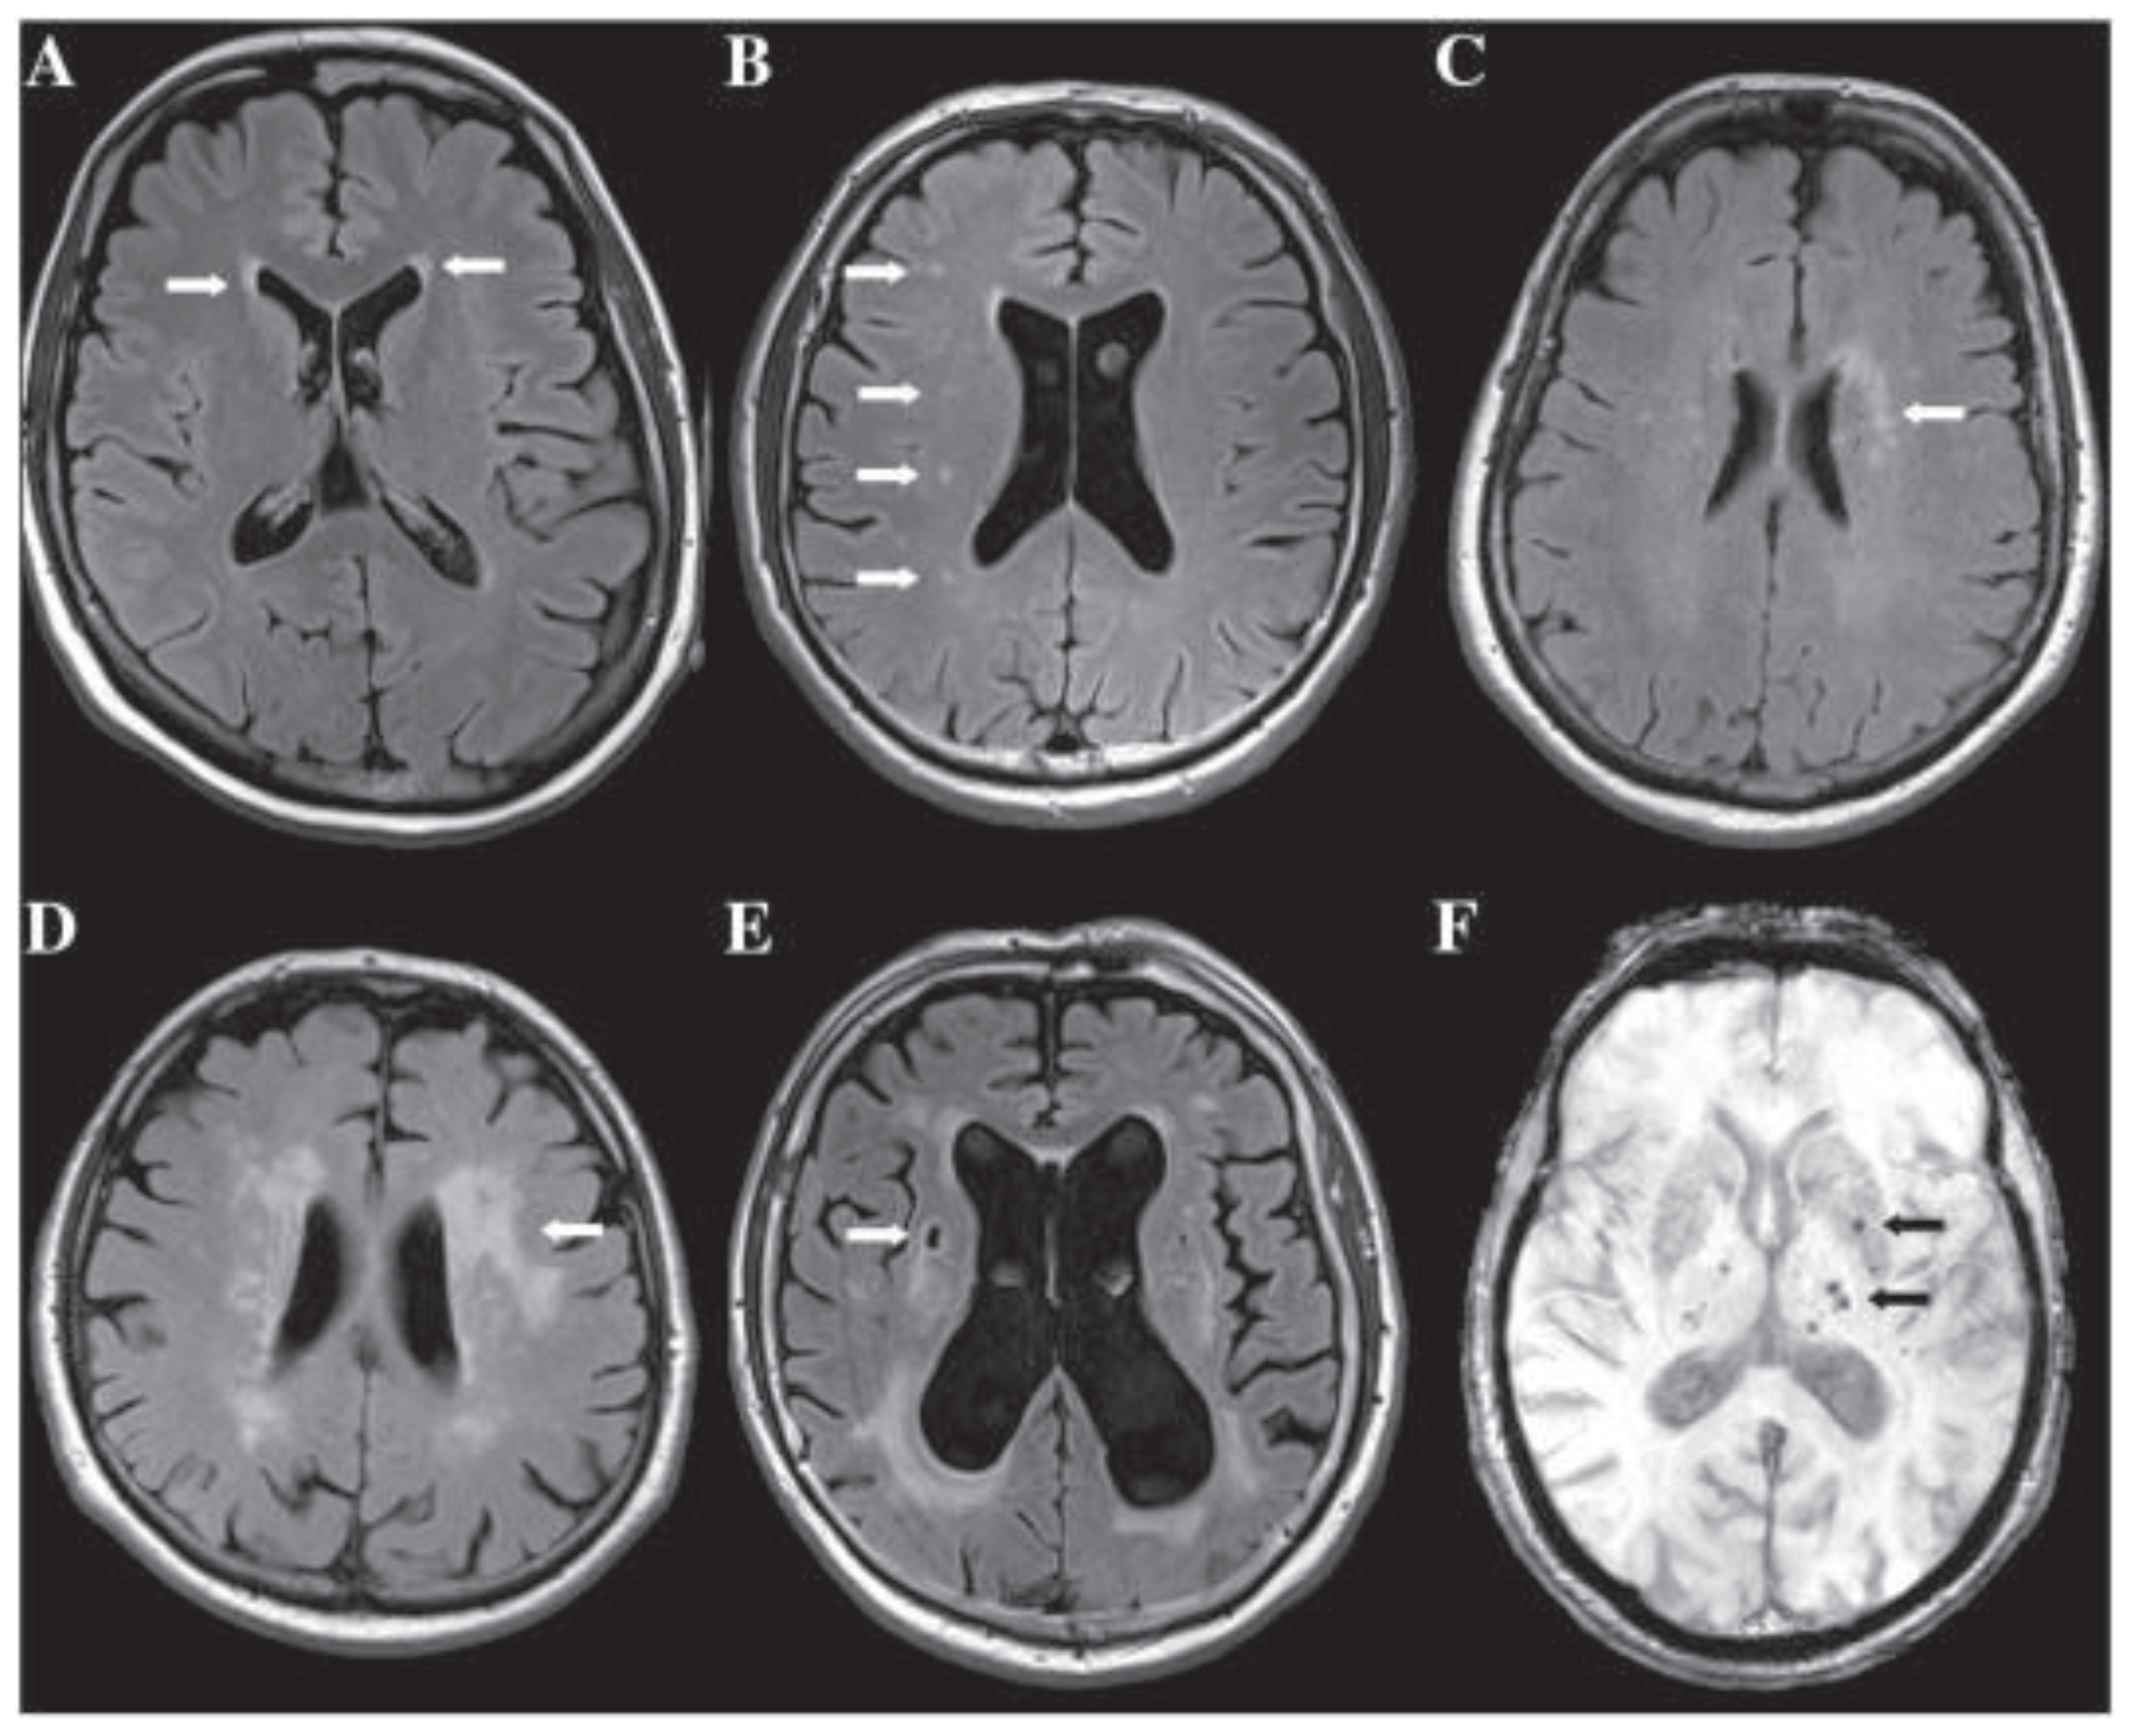

- Gorelick, P.B.; Scuteri, A.; Black, S.E.; DeCarli, C.; Greenberg, S.M.; Iadecola, C.; Launer, L.J.; Laurent, S.; Lopez, O.L.; Nyenhuis, D.; et al. Vascular Contributions to Cognitive Impairment and Dementia. Stroke 2011, 42, 2672–2713. [Google Scholar] [CrossRef] [PubMed]